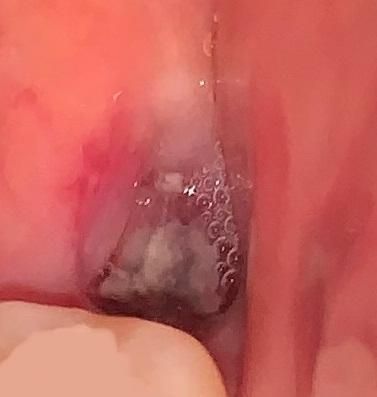

사랑니 발치했는데 드라이소켓 가능성이 있나요?

똑바로 난 사랑니라 딱히 절개없이 바로 발치하였습니다.

발치한지 1주일정도가 되었는데도 가만히 있어도 발치부위 잇몸과 턱이 욱신거리는 느낌이 계속됩니다.

드라이소켓일 가능성이 있을까요? 아니면 발치부위가 치유되는 과정일까요?

• 1번 째 사진